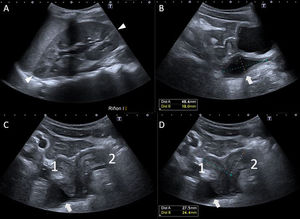

RM de pelvis. A) Secuencias potenciadas en T2 axial y B) ampliación de la A) centrada en la región de interés. Útero didelfo con tabique vaginal derecho con morfología infantil prepuberal. Los cuerpos uterinos (1 derecho/2 izquierdo) se encuentran en anteflexión, cada uno lateralizado hacia un lado. C) Secuencia potenciada en T2 sagital oblicuo y D) secuencia potenciada en T2 coronal oblicuo centrado en el cérvix del útero derecho. Cuello de útero derecho (1, flecha) con desembocadura en hemivagina derecha dilatada y con contenido hiperintenso (líquido) en su interior (*), correspondiente con la imagen quística descrita en ecografías previas. No demuestra contacto con el periné. E) Secuencia potenciada en T2 sagital oblicua centrada en hemivagina izquierda. Cuello de útero izquierdo (2) con continuidad con una estructura alargada colapsada (punta de flecha) que alcanza periné, sugestiva de corresponder a hemivagina izquierda, aparentemente permeable. F) Secuencia T1 VIBE tras la administración de contraste en fase parenquimatosa objetivándose riñón izquierdo único, compensador.

B: bazo, H: hígado, O: ovario derecho, R: recto, RI: riñón izquierdo, V: vejiga.

Presentación del casoPresentamos el caso de una niña prepuberal de 10 años en seguimiento pediátrico que fue diagnosticada prenatalmente de riñón izquierdo único. Durante el seguimiento ecográfico posnatal, se detectó una estructura tubular con contenido líquido-anecoico en la pelvis, con estrechamiento hacia la uretra derecha, planteando inicialmente un diagnóstico diferencial entre resto mesonéfrico/uracal atípico, riñón derecho ectópico y atrófico. Se repitió la ecografía posteriormente (fig. 1.), en la que se identificó la presencia de un útero bicorne bicollis con colección líquida cerca de la vagina. La resonancia magnética (RM) confirmó un útero didelfo con hemivagina derecha ciega y hemivagina izquierda permeable (fig. 2). Se realizó vaginoscopia para confirmar la permeabilidad de la hemivagina izquierda y, actualmente, está en lista de espera para tratamiento definitivo con vaginoplastia.